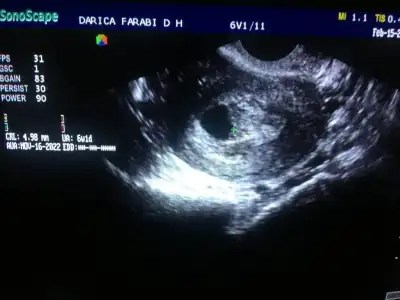

Şimdilik devlete gidiyorum canım cihazı sen düşün çıktı bile verenlerden değil ama keseyi hemen gördü çok küçük olmasına rağmen 3.1 mm dediCihaz çok önemli. 7+6 da kese içinde bebeği göremedi benim doktorum bu yüzden

Benim 5+0 da sadece kese gördü 3.1 mm dedi ama bebekten bahsetmedi bende heyecqndan sormadım belkide bebekte vardı bilemiyorum ben yumurtlama günümü biliyorum 14. Gün değil 18. Gün çatlama oldu 4 gün bile farkeder diye düşünüyorum 6+2 de inş benee kalp atışını görebilirim5+5te bebeğimizi de kalp atışını gördük keseyle ama duymak için doktor beklemek istedi. Ne güzel belirti olmaması, o belirtiler bir süre sonra yorucu olabilir ne kadar az belirti o kadar iyi :)